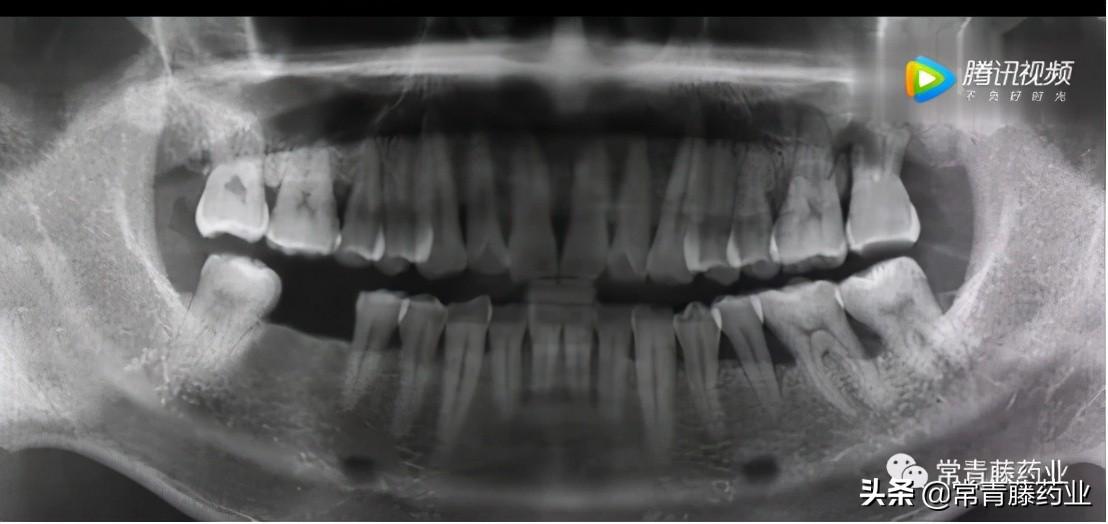

今天給大家科普一下種牙的知識(shí)!在種牙開始之前需要進(jìn)行口腔檢查和全景片、頜骨CT拍攝以確定牙周是否有炎癥、牙槽骨頭是否擁擠以及牙體情況等。(如下圖)